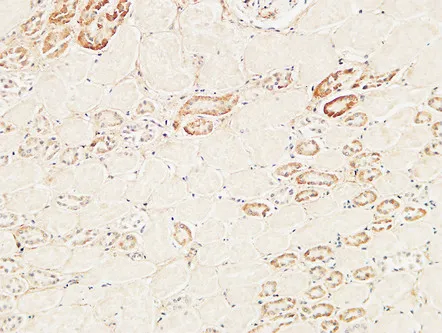

MDM2 Rabbit Polyclonal Antibody

Cat: APRab13758

CD63 Rabbit Polyclonal Antibody

Cat: APRab08430